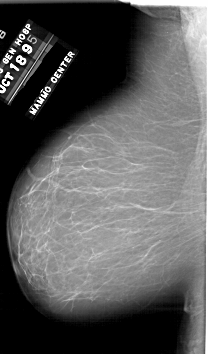

A_1748_1.RIGHT_CC

RIGHT_CC LINES 6346 PIXELS_PER_LINE 3496 BITS_PER_PIXEL 12 RESOLUTION 43.5 OVERLAY